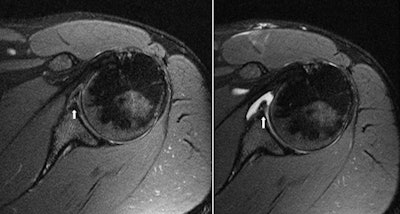

| MR (left) and MR arthrogram (right) are from the same patient with an anterior labral tear. The condition was repaired with surgical tacking. Images courtesy of Thomas Magee, MD. |